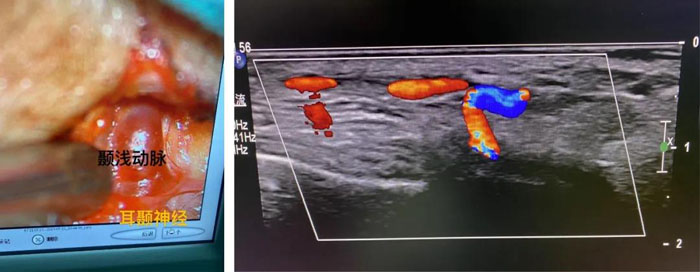

患者女,65歲,雙側(cè)顳部及枕部持續(xù)搏動性跳痛30余年,就診我院頭面痛門診。郝懷勇主治醫(yī)師經(jīng)過細(xì)致的體格檢查,發(fā)現(xiàn)引起她頭痛的根源是顳部的耳顳神經(jīng)和枕部的枕大神經(jīng)。借助術(shù)中超聲,在李永濤主任醫(yī)師指導(dǎo)下,郝懷勇主治醫(yī)師在顯微鏡下為患者行“耳顳神經(jīng)及枕神經(jīng)微血管減壓術(shù)”。術(shù)中發(fā)現(xiàn)神經(jīng)與周邊纖維筋膜組織黏連緊密,顯微鏡下松解神經(jīng)被卡壓部位,并處理纏繞神經(jīng)的血管。術(shù)后疼痛消失,門診隨訪無復(fù)發(fā)。